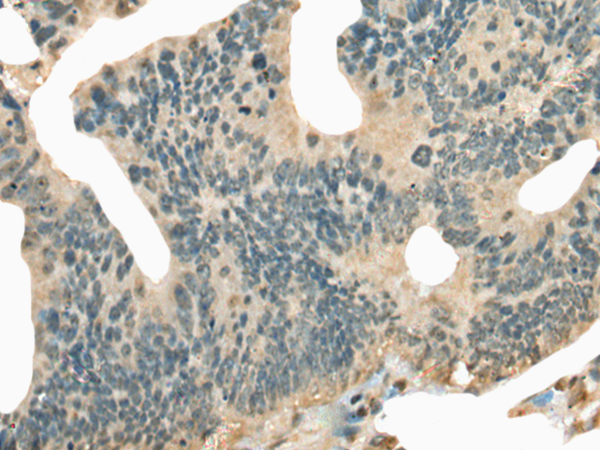

分类: 科研抗体货号: P02407别名: hSAD1应用: IHC反应种属: Human, Mouse, Rat